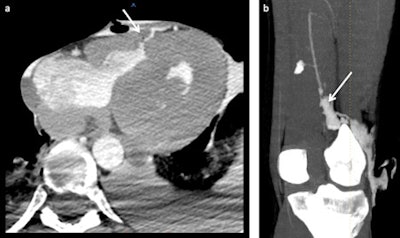

Reconstruction of sharp trauma lesions resulting from stab wounds. The first case (a) shows a stab wound trajectory in the chest with an intramyocardic trajectory. The second case (b) shows a stab wound in the left leg with a lesion of the popliteal artery (arrow in b).The most important study at the moment is the validation study of MPMCTA, in which 500 cases investigated in different centers are being investigated. This study will be submitted for publication in spring 2014, Grabherr noted in an email to AuntMinnieEurope.com.